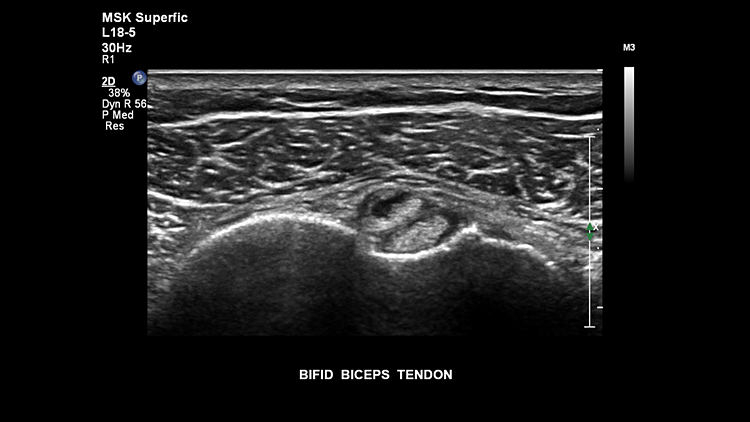

Перелом большеберцовой кости, L18-5

Сухожилие двуглавой мышцы бицепса